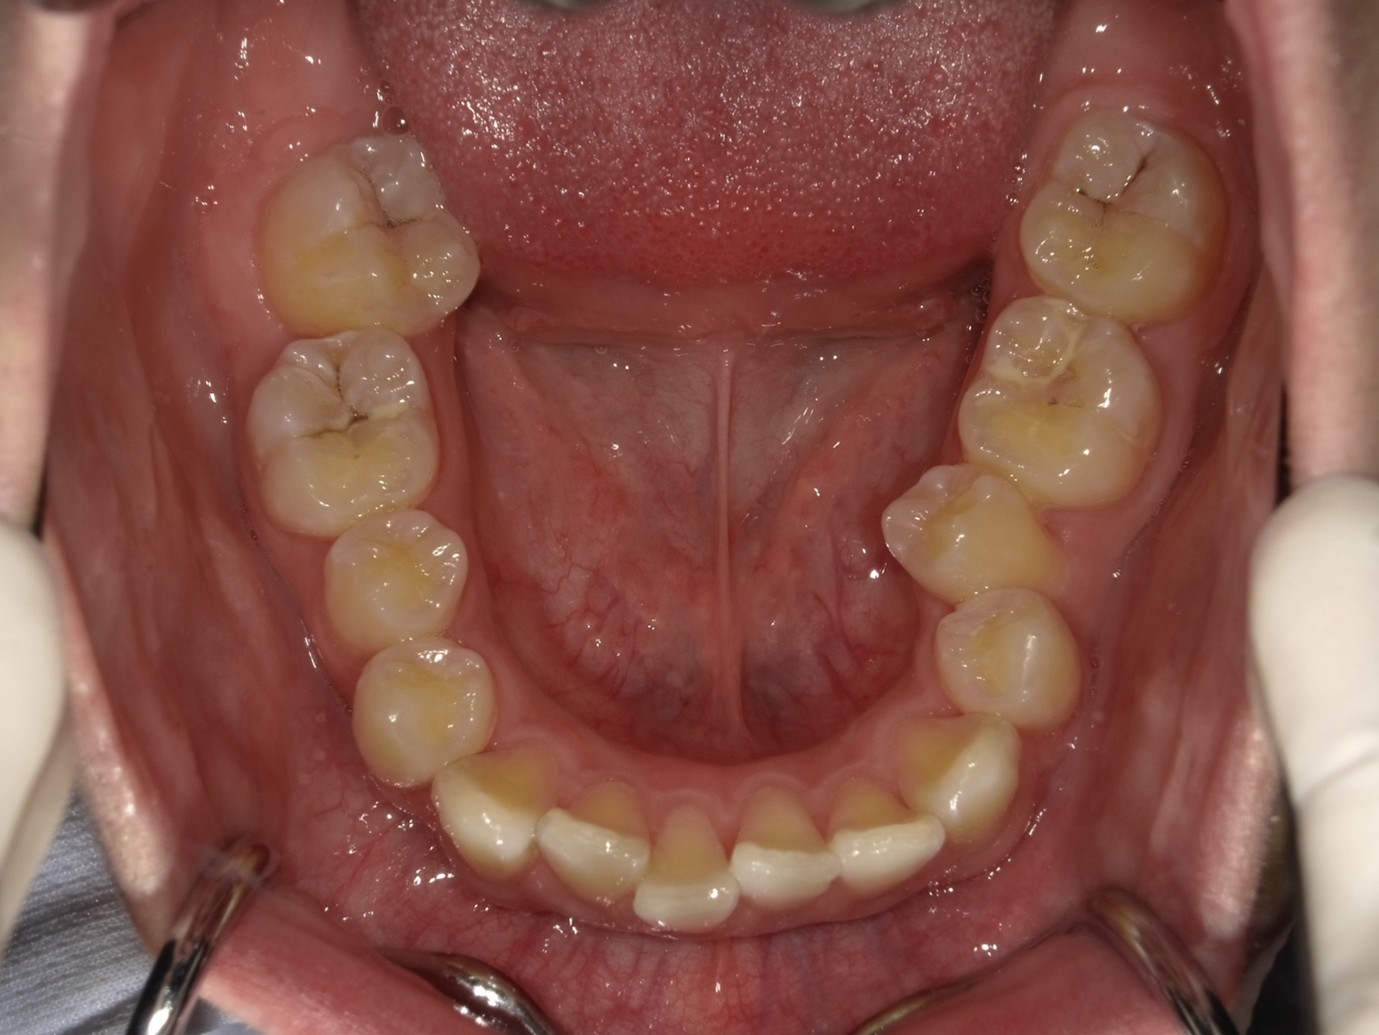

| 症例分類 | 過蓋咬合 |

|---|---|

| 主訴 | 他の歯科医院で咬み合わせを指摘された |

| 年齢 | 10歳10ヶ月 |

| 性別 | 男性 |

| 抜歯部位 | なし |

| 使用装置 | 拡大装置、咬合斜面板(取り外し式の矯正装置) |

| 治療期間 | 3年4ヶ月 |

| 保定装置 | 咬合斜面板 |

| 費用 | 相談料0円、検査料55,000円 動的矯正治療費330,000円 調整料6,600円×30回分 保定装置料0円 |

| リスク・注意点 | 上の顎の大きさに対して下の顎が小さく、過蓋咬合が生じています。これらを改善するために、幅の狭搾している歯列を側方に拡大したのち、下顎の成長を促進しました。

歯の動き方には個人差があり、予想された治療期間が延長する可能性があります。 治療中は矯正歯科装置が歯の表面に付いており、歯が磨きにくくなるため、むし歯や歯周病が生じるリスクが高まります。ハミガキを適切に行ってお口の中を常に清潔に保ち、さらに、かかりつけ歯科医に定期的に受診することが大切です。 矯正歯科装置の使用状況、定期的な通院など、矯正歯科治療には患者さんの協力が必要であり、それらが治療結果や治療期間に影響します。 治療の経過によっては当初予定していた治療計画を変更する可能性があります。保定装置の装着時間が十分確保できない場合、歯並びや、咬み合せの「後戻り」が生じる可能性があります。 上下両側第二大臼歯の萌出を観察する必要があります。(治療後の写真は成人矯正開始直前の資料です。) |